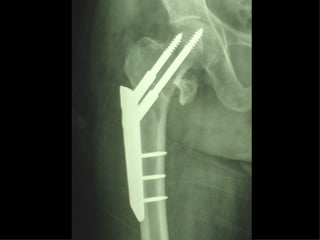

La placca a compressione percutanea (PC.C.P.) di Gotfried è un mezzo di sintesi studiato per assicurare un “impattamento controllato” delle fratture pertrocanteriche grazie alle due viti telescopiche prossimali che garantiscono una ottima stabilità rotazionale

Con la placca di Gotfried non si è mai riscontrato un danno iatrogeno del muro laterale e nessun collasso della frattura.Ciò è dovuto al fatto che i fori per l’applicazione delle due viti prossimali sono di piccolo diametro (9 mm) rispetto ai 16-32 mm necessari per introdurre la vite cefalica di un chiodo endomidollare o di una vite-placca a compressione.

La placca PC.C.P. viene inoltre applicata per via percutanea attraverso due piccole incisioni ottenendo in tal modo un minimo trauma chirurgico ed una  perdita di sangue estremamente ridotta in pazienti che per l’età  sono già in condizioni  critiche

Dal Gennaio 2005 ad Agosto 2006 110  placche di Gotfried Età media  : 78 anni (range 29-94) Tempo chirurgico: 30 minuti (range 12-45) IMMEDIATA CONCESSIONE DEL CARICO